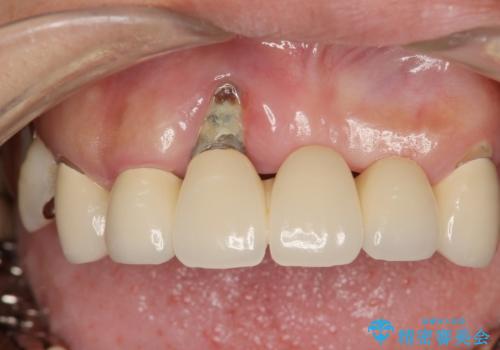

歯周病 全顎治療

- 前歯の見た目、入れ歯による噛めないことの改善を求めて来院されました。

検査により全顎的な歯周病治療、欠損のインプラント補綴、根管治療が必要な状態であることをお伝えし、治療を計画します。

インプラント治療の注意事項(リスク・副作用など)

- 外科手術のため、術後に痛みや腫れ、違和感を伴います

- メンテナンスを怠ったり喫煙により、お口の中に大きな悪影響を及ぼすインプラント周囲炎等にかかる可能性があります